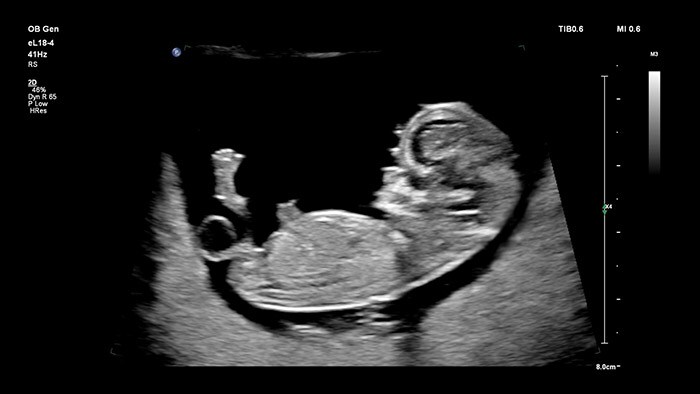

Датчик Philips eL18-4 с функцией визуализации Microflow преодолевает препятствия, связанные с 2D-визуализацией высокого разрешения и сверхчувствительным обнаружением кровотока для оценки общего состояния здоровья плода на ранних сроках беременности, т. е. тогда, когда превосходное разрешение и надежность диагностики имеют ключевое значение. В высшей степени универсальный, разработанный исключительно для акушерства, ультразвуковой датчик V9-2 использует мощь технологии кристаллов PureWave для обеспечения превосходной визуализации в режимах 2D и 3D, сохраняя при этом легкий для своего класса вес.